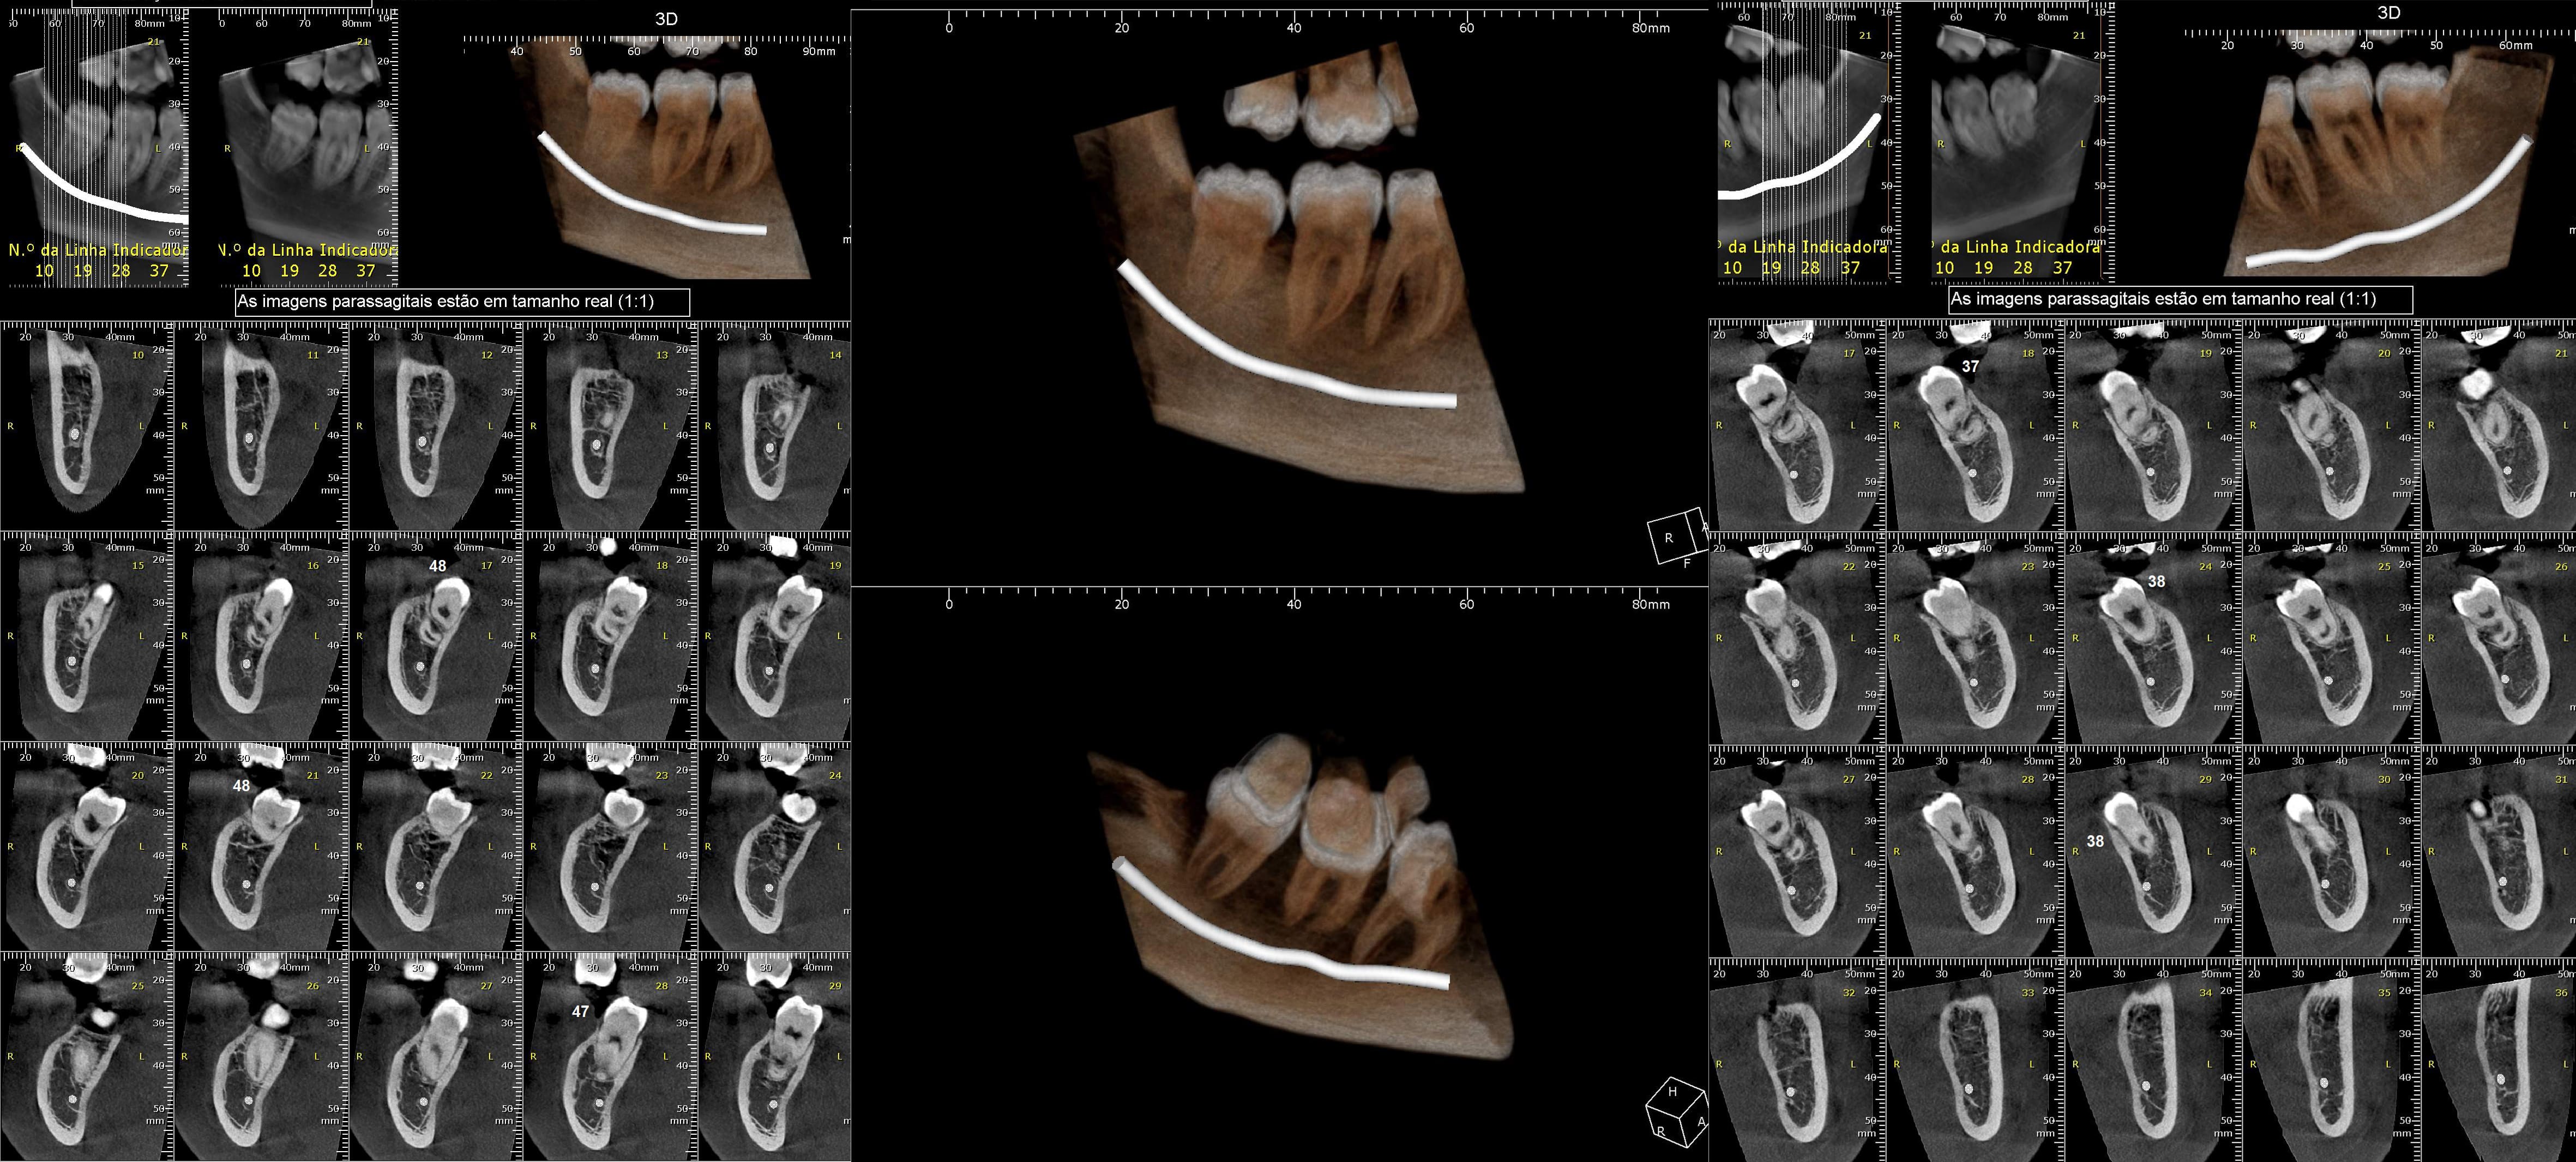

TOMOGRAFIA CONE BEAM: